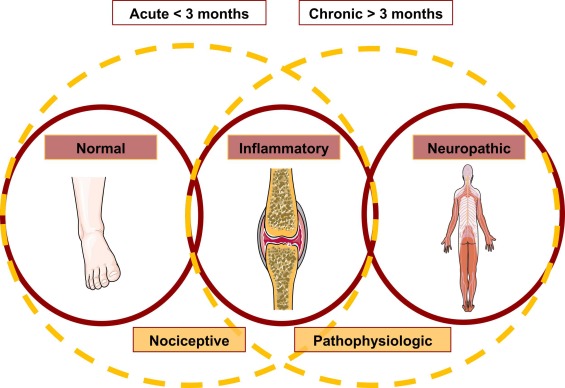

Arthritic changes – Arthritis is related to a condition of painful joints due to inflammation or swelling. A type of arthritis is rheumatoid arthritis, it is an autoimmune disease where the immune system attacks the joints, starting with the lining of joints. Rheumatoid arthritis is heavily related to lung problems, about 80% of arthritic patients have lung-related issues, making it the second leading cause of death with rheumatoid arthritis patients. Rheumatoid arthritis caused lung problems are most commonly extra-articular i.e., outside of the joints and involves pulmonary nodules; damage to the lung airways, pleural effusion and interstitial lung disease. In rheumatoid arthritis associated interstitial lung disease the auto-immune system gets over active and attacks the lungs and causes scarring. With time, the scarring build-up leads to difficulty breathing and reduced lung function.

Emphysema – With age there are various structural, functional and immunological changes that take place within the respiratory system. The anatomical changes include thoracic spine and chest wall distortion leading to impairment in the respiratory system and heavier breathing load. Due to the loss of its supporting structures, the lung parenchyma faces “senile emphysema” i.e., dilation of air spaces. In addition to that, the airway clearance needed for effective cough is also hindered due to the loss of strength in the respiratory muscles.

Elastcitiy (compliance) – Aging is strongly associated with a significant decrease in elastic recoil and fibrous strength. With age, there is inevitable reduction in the thoracic compliance and augmentation in lung compliance. Thoracic (chest wall) compliance regulates the elastic load during inhalation whereas the lung compliance regulates the rate and force of exhalation. With aging there are significant structural changes to the thoracic spine and cage which ultimately leads to depletion in chest wall compliance.